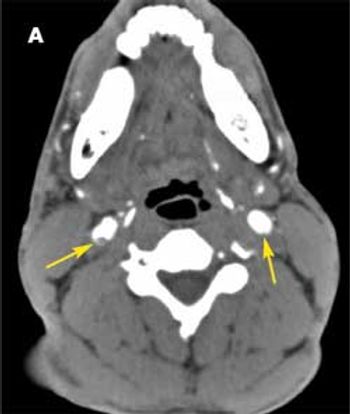

A 26-year-old woman at 30 weeks’ gestation presented to the emergency department with a throbbing frontal headache of 1 month’s duration. She had also had peripheral blurred vision for the past 2 weeks. Acetaminophen initially decreased her pain but was no longer effective. She had had a previous miscarriage.